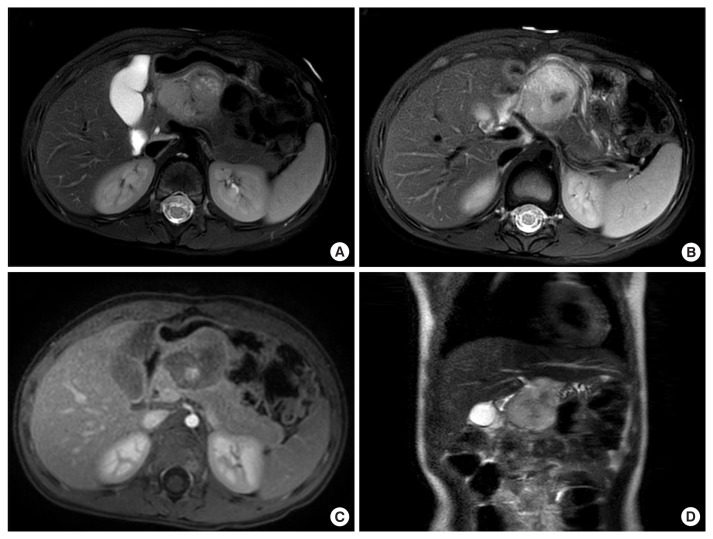

Extraosseous Ewing sarcoma is a rare and aggressive malignancy belonging to the Ewing sarcoma family of tumors, primarily affecting soft tissues such as the pelvis, retroperitoneum, and chest wall. Although it predominantly involves these soft tissues, extraosseous Ewing sarcoma can also occur in solid organs, including the pancreas. Here, we present a rare case of a 4-year-old girl diagnosed with primary extraosseous Ewing sarcoma of the pancreas.

Abstract Image